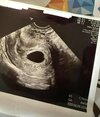

Puste jajo płodowe

Hej, 14.01 byłam u ginekologa z myślą, że może już coś zobaczę… jak się okazało - puste jajo płodowe bez zarodka. Według USG 6w5d, wymiar pęcherzyka ciążowego 17,6cm. Za tydzień wizyta kontrolna, ale tak się stresuje, że już nie wiem co myśleć… czy któraś z Was miała podobną sytuację i ja się to zakończyło?